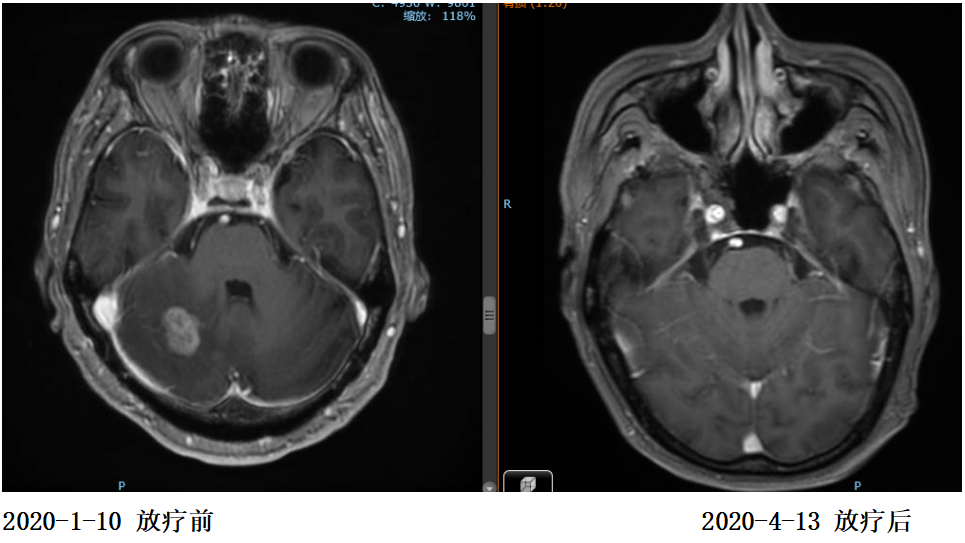

2020年1月患者出现头痛症状,复查脑MR示:枕叶及右侧小脑半球多发结节,结合病史考虑转移灶。

2020年1月13日开始对左侧枕叶及右侧小脑转移灶进行放疗,PTV-GTV=44.5Gy/9F

复查:2020.4复查颈部CT及全腹部+盆腔MR大致同前,脑MR示病变较前明显缩小,评估PR。

2020年11月4日复查颈部胸腹盆CT大致同前,脑转移灶明显缩小,继续赫赛汀联合希罗达维持治疗。